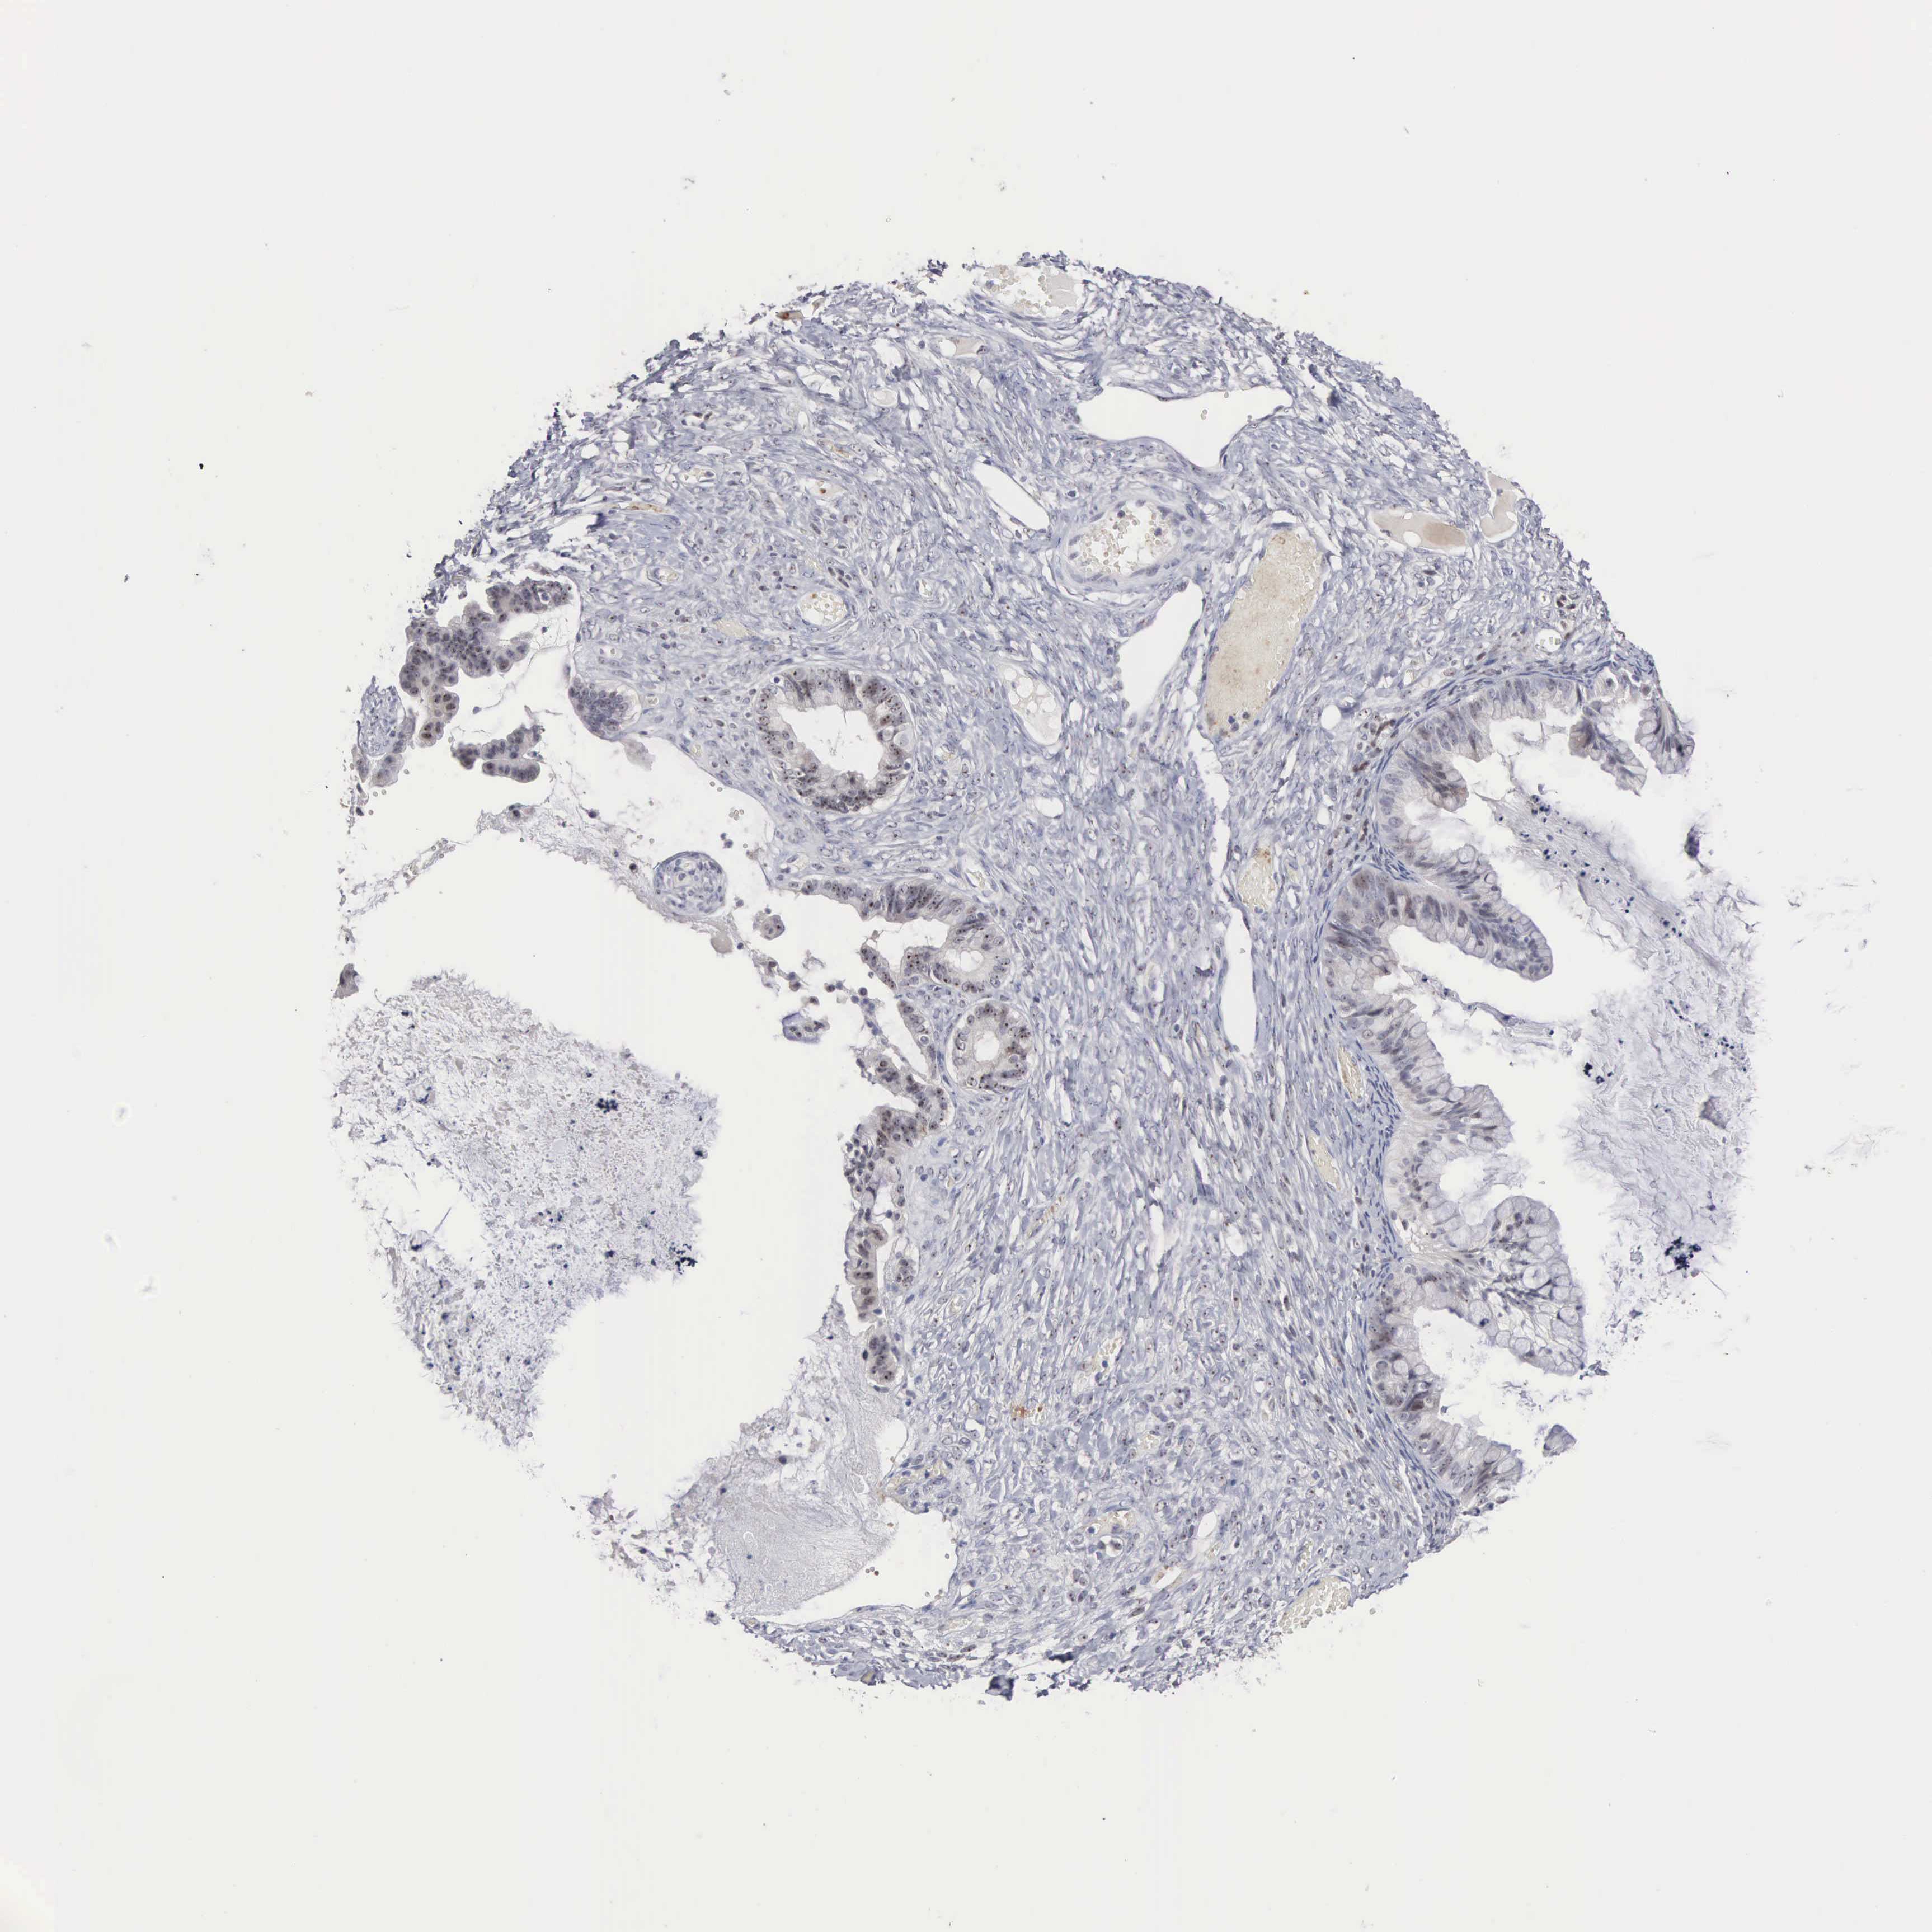

OVARIAN CANCER - Protein expressioni

A mouse-over function shows sample information and annotation data. Click on an image to view it in a full screen mode. Samples can be filtered based on level of antibody staining by selecting one or several of the following categories: high, medium, low and not detected. The assay and annotation is described here.

Note that samples used for immunohistochemistry by the Human Protein Atlas do not correspond to samples in the TCGA dataset.

Antibody stainingi

Antibody staining in the annotated cell types in the current human tissue is reported as not detected, low, medium, or high, based on conventional immunohistochemistry profiling in selected tissues. This score is based on the combination of the staining intensity and fraction of stained cells.

Each image is clickable and will lead to virtual microscopy that enables deeper exploration of all samples and also displays staining intensity scores, fraction scores and subcellular localization as well as patient and tissue information for each sample.

Antibody HPA000779

Cystadenocarcinoma, mucinous, NOS

Carcinoma, endometroid

Cystadenocarcinoma, serous, NOS